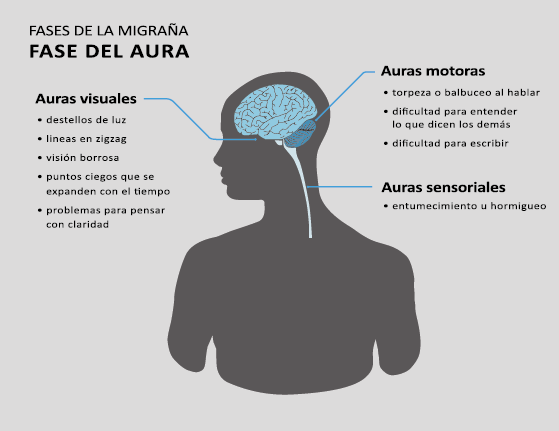

El aura de la migraña, al menos en su sentido clásico, tiene relación con la depresión cortical que se propaga por la corteza cerebral y participa como un actor paralelo cuando se producen las crisis. (Figura 2)

Alrededor de un tercio de los migrañosos experimentan déficits neurológicos transitorios: el aura de la migraña, en el contexto de sus episodios migrañosos(13). La Clasificación Internacional de la Cefalea 3 Beta, define el aura migrañosa como uno o más déficits neurológicos transitorios, completamente reversibles, de los cuales al menos uno debe tener una localización unilateral, que se desarrollan durante 5 minutos o más y cada déficit dura entre 5 y 60 minutos.

El 26% de los pacientes tiene al menos una de tres auras que dura más de una hora. La forma en que los enfermos suelen lidiar con su migraña es una clara indicación de su hipersensibilidad a la estimulación sensorial. Algunos informarán que durante un ataque se irán a la cama, apagarán las luces y evitarán cualquier tipo de estimulación sensorial de luz, sonido, tacto u olor, como si estuvieran cerrando todas las entradas sensoriales posibles. De hecho, en la clasificación de la migraña se incluye que acompañando la migraña debe haber al menos fotofobia, fonofobia, náuseas y vómitos(38). La fotofobia es uno de los síntomas claves no relacionados con el dolor de cabeza que definen la migraña. Los pacientes generalmente describen que la luz es demasiado brillante (sensibilidad anormal a la luz) o incluso dolorosa al causar o empeorar el dolor de cabeza o los ojos (alodinia fotótica). Incluso en los períodos intercríticos toleran menos luminosidad que los controles sanos y activan la corteza visual (cuneus y giro lingual) cuando se exponen a diferentes intensidades luminosas. La fotofobia en la migraña puede tomar la forma de alodinia fótica, donde la luz en sí es desagradable sin dolor, o hay hipersensibilidad fotótica. Puede mostrar fenómenos positivos (espectros de fortificación), negativos (escotoma), o ambos. Se encuentra en más del 90% de los casos, generalmente comienza antes de la fase de dolor, pero también puede ocurrir al mismo tiempo o incluso independientemente de cualquier dolor de cabeza. Otras auras descritas son el aura sensorial, motora, del habla, del tronco encefálico y retiniana. Demarquay et al.(19) evaluaron el procesamiento olfativo en migrañosos con hipersensibilidad olfativa habitual y encontraron que durante la estimulación del olor, los migrañosos habían aumentado el flujo sanguíneo cerebral en el polo temporal izquierdo. Por lo tanto, algunos síntomas específicos, como la hipersensibilidad olfativa, se asocian con una respuesta cortical única incluso fuera de los ataques. Es muy común la superposición de las fases del aura y del dolor de cabeza. En los que padecen síntomas de aura motora, como en la migraña hemipléjica, los síntomas de aura suelen mostrar una duración más prolongada de hasta 72 horas. En conjunto, estos datos sugieren que varias áreas corticales y subcorticales en el cerebro de las personas con migraña responden de manera diferente a los estímulos externos en comparación con los controles sanos. Esto podría implicar que el cerebro de una persona con migraña es “hiperexitable”(20) con anomalías funcionales precondicionadas que se exacerban concertadamente durante los ataques de migraña. Sin embargo, se debe mantener una mente abierta y evaluar la presencia de factores de riesgo cardiometabólico conocidos o desconocidos por el paciente, con el fin de considerar los diagnósticos diferenciales. (Figura 8)

Se cree que una onda transitoria de despolarización neuronal de la corteza (Figura 9), la depresión de propagación cortical (CSD), es el mecanismo cerebral fisiopatológico subyacente al fenómeno clínico del aura de la migraña. Leão(21) estableció un mecanismo subyacente hipotético. Luego de haber estimulado eléctricamente la corteza de conejo y encontrar una depresión EEG que se propagaba a una velocidad similar de 3 mm/min centrífugamente desde el sitio de estimulación sugirió que podría ser la base del aura migrañosa. Esta hipótesis está fundamentada en la correlación entre las características neurofisiológicas de una CSD, su propagación retinotópica en la corteza visual y las características y dinámicas de los déficits visuales(14, 15) y en las observaciones indirectas derivadas de los estudios de imágenes que respaldan aún más este concepto(16) Sin embargo, sobre la base de la comprensión actual de la migraña, es poco probable que la CSD esté involucrada en el inicio del síndrome completo de la migraña(17).